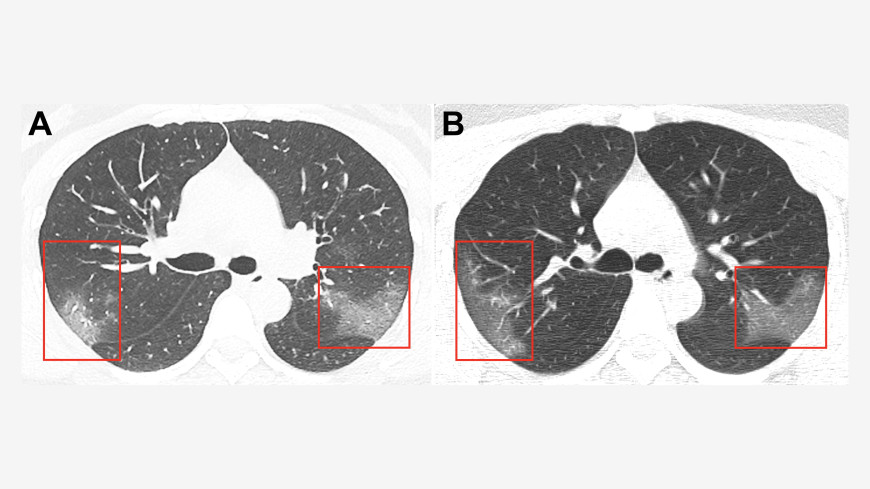

Phim chụp phổi nạn nhân bị lây nhiễm virus corona. -Ảnh: Pubs rsna org |